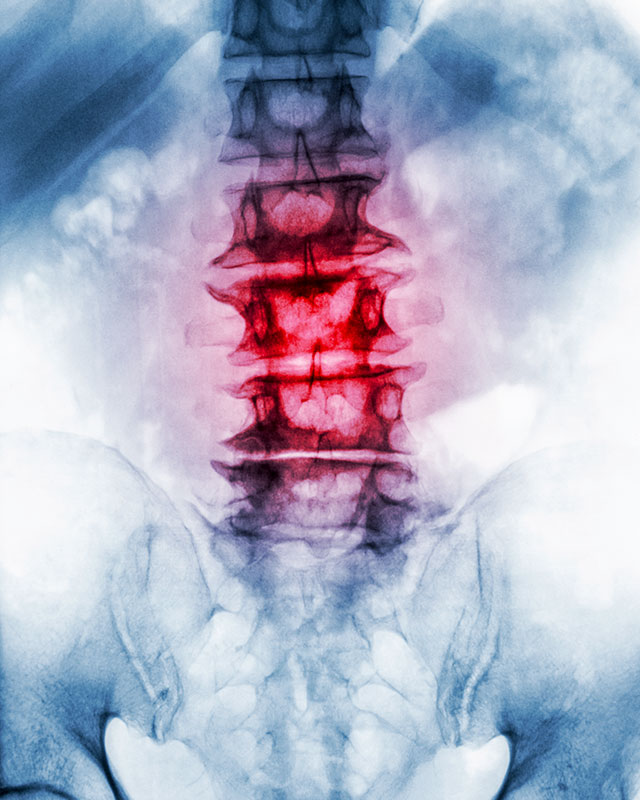

Chiropractic is a health profession that focuses on the spine and other joints of the body and their connection to the nervous system. It’s based on the premise that good health depends substantially upon a normally functioning nervous system. Body parts, organs and cells function mostly under the control of nerve impulses to and from the brain and spinal cord.

When there is interference to this normal transmission, normal function is interfered with, and malfunction may result, predisposing a part of your body to pain or other disorder. In chiropractic this is called joint dysfunction or vertebral subluxation. Effects of joint dysfunction ›

The spinal cord leads to 31 pairs of spinal nerve roots that exit the spinal bones. Although the spine offers support and protection for the delicate and sensitive spinal cord and the nerve roots, it can also cause nerve interference when the spinal joints are jammed. You may have a ‘pinched’ or ‘irritated’ nerve.